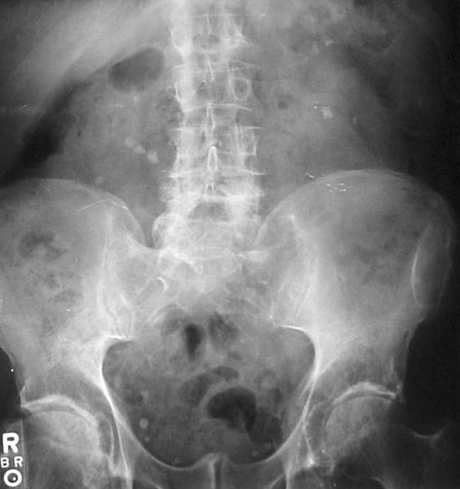

Struvite/Staghorn Stones (~15%)

- Large, moulded to renal pelvis/calyces (“staghorn”)

- Associated with squamous metaplasia

- Often due to chronic infection

- Abdominal X-ray (AXR):

- Detects radio-opaque stones (e.g. calcium)

Nevit Dilmen, CC BY-SA 3.0 <https://creativecommons.org/licenses/by-sa/3.0>, via Wikimedia Commons